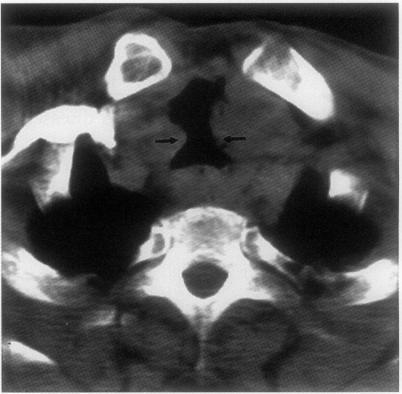

Lethal tracheal dissolution during treatment for thyroid lymphoma.

• A case of primary thyroid T cell lymphoma leading to lethal tracheal perforation during chemotherapy is described.